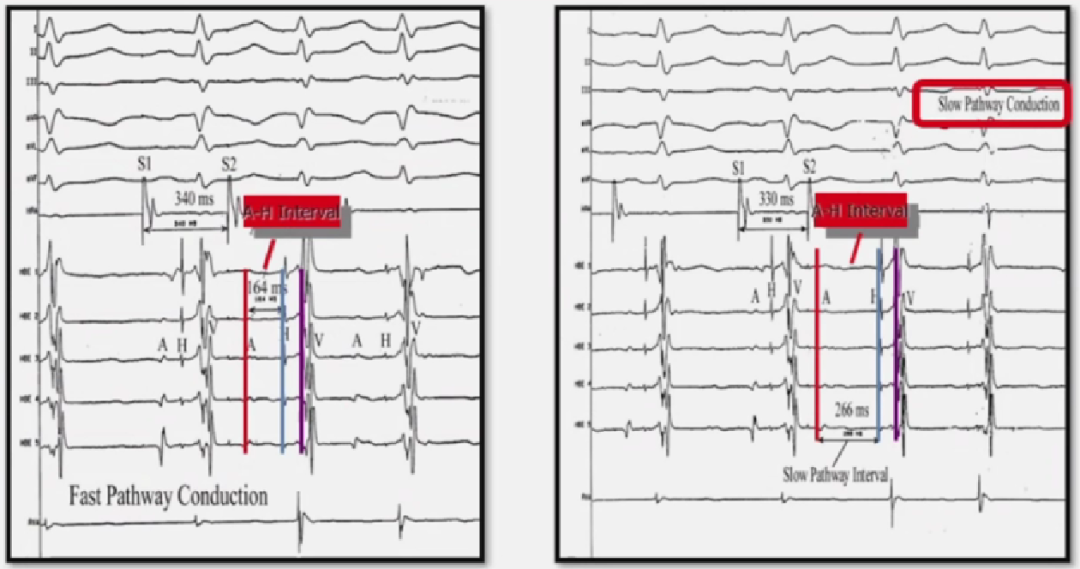

AVNRT生理特性:A - H Jump

A-H Jump(房室结跳跃现象)

当 S1S2刺激周期缩短10ms(从340ms → 330ms)时,A-H间期突然显著延长(图中虚线箭头所示)。

-

这种非渐进性、跳跃式延长(通常 ≥ 50ms)是诊断房室结双径路(Dual AV Nodal Pathways)的直接电生理证据。

机制:房室结双径路传导

快径路(Fast Pathway):

传导速度快,但不应期长(较早进入不应期)。

→ S1刺激时,冲动经快径下传,A-H间期较短(图中上方路径)。 -

慢径路(Slow Pathway):

传导速度慢,但不应期短(可传导更早的冲动)。

→ S2刺激周期缩短时,快径路进入不应期,冲动"跳跃"至慢径路下传,导致A-H间期显著延长(图中下方路径)。

A-H Jump是诱发AVNRT的典型起点:

冲动经慢径路下传后,若快径路恢复传导,可能形成"慢径路前传→快径路逆传"的折返环,从而引发心动过速。

S1(基础刺激) → 快径传导 → A-H间期正常(短)。

S2(早搏刺激) → 快径阻滞 → 跳跃至慢径传导 → A-H间期显著延长("Jump")。